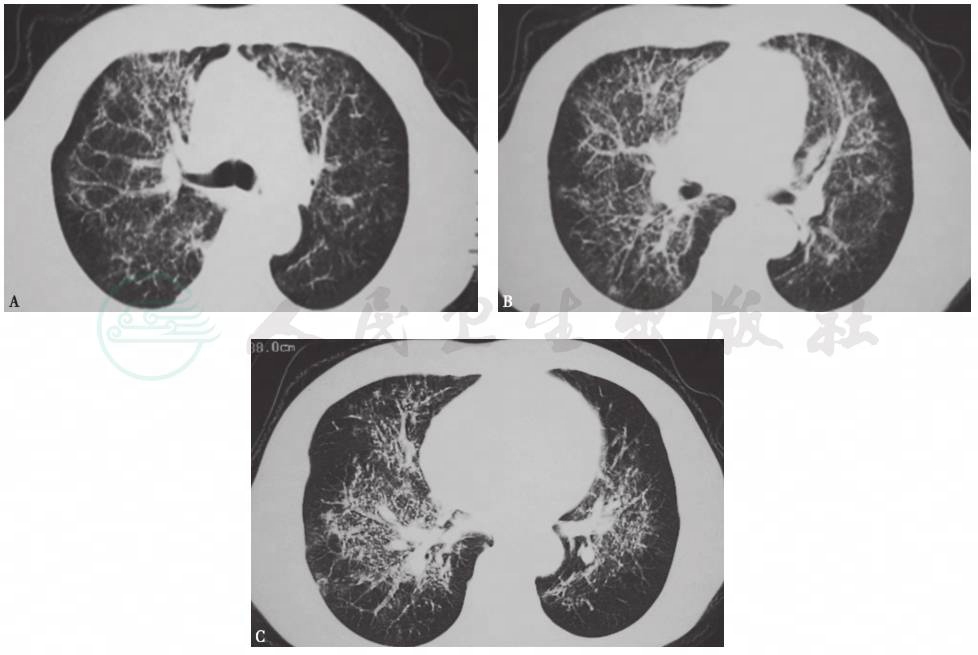

入院时胸部HRCT示右中上肺大片炎症伴实变影,右侧胸腔积液伴双侧胸膜增厚、粘连(图1);抗感染治疗2周后复查胸部HRCT示病变较前明显进展,可见双肺多发片状影及结节影,部分病变内可见支气管充气征,双侧少量胸腔积液(图2)。

图2 入院治疗2周后复查胸部HRCT表现

HRCT示双肺以中上肺为主的多发实变影、结节影及磨玻璃影,部分病变内可见支气管充气征,双侧少量胸腔积液